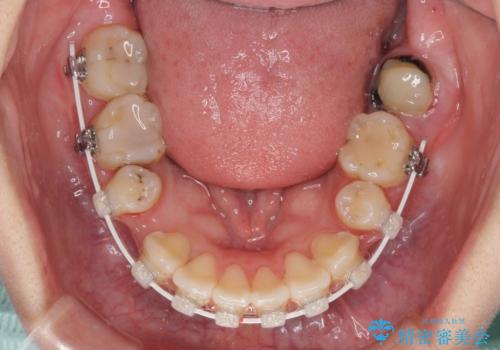

- ハーフリンガル

目立たない装置を希望されたので、上顎が裏側装置のハーフリンガルを選択し、上下左右の小臼歯(計4歯)を抜歯して矯正治療を行うこととしました。

また、左下の奥歯は抜歯が必要な歯であったため、矯正治療中の良いタイミングで抜歯とインプラント埋入を行い、矯正治療後にオールセラミッククラウンで補綴治療を行うこととしました。

デコボコの解消までは非常にスムーズでしたが、咬合力が強いためか、スペースを閉じるまでに長い期間を要しました。

矯正治療途中にインプラント埋入と仮歯の装着を行ったことで、しっかりとした奥歯の咬み合わせで終了させることができました。